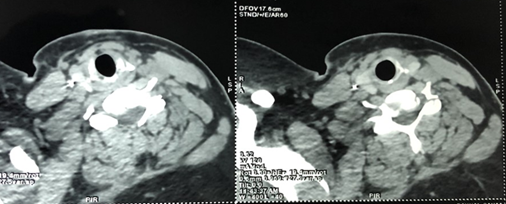

A cervico-thoracic CT-scan was done objectifying, in addition to multiple

subcutaneous metallic foreign bodies (Figure

2), a metallic wire which has migrated in the supra clavicular area and

reached the carotid region, between the internal carotid artery and the

internal jugular vein and reaching the upper part of the thorax, measuring

approximately 4cm (Figure 3).

Figure

3: Cervical CT-scan –

cross section showing cervico-thoracic steel wires embedded between the

internal carotid artery and the internal jugular vein